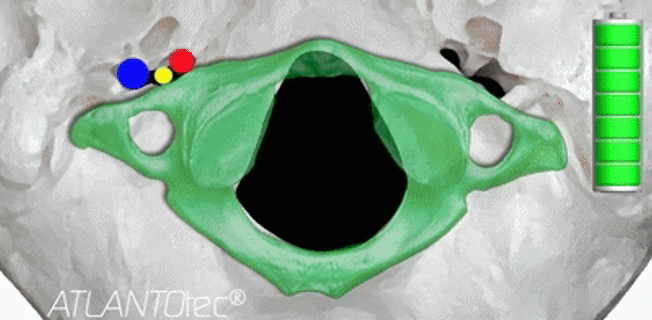

머리와 목의 경계부 즉 후두골–C1–C2 구간은 뇌간과 척수가 직접 이어지는 지점입니다.

이 부위가 틀어지면 연수와 척수에 영향을 줄 수 있고 추골동맥을 따라 흐르는 뇌혈류의 흐름이 제한될 수 있습니다.

그래서 이러한 기능이상 파악을 위해 항상 X-ray로 상부경추(C0, C1, C2)의 정렬을 가장 먼저 확인합니다.

이는 정확하게 파악하고 치료하기 위함이며 상부경추(C0·C1·C2)의 회전 각도와 틀어진 방향을 수치화해

시술 전후의 변화를 비교하면 환자분이 느끼는 안정감이 실제 구조 변화와 함께 일치하는 걸 확인할 수 있기 때문이죠.